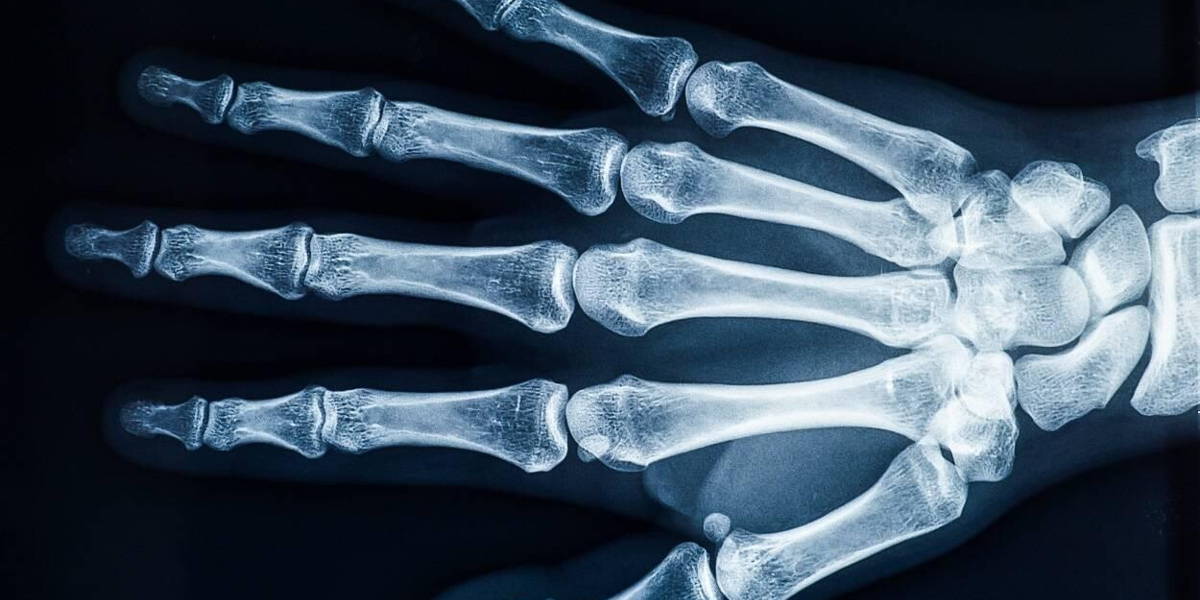

Wanneer een patiënt met een botbreuk op de huisartsenpost binnenkomt, kan de dienstdoende huisarts nu buiten kantooruren rechtstreeks diagnostiek aanvragen bij de afdeling radiologie van het CWZ. Dankzij de inzet van artificial intelligence (AI) van Gleamer BoneView, het programma dat de foto’s beoordeelt, hoeft de SEH-arts namelijk niet meer betrokken te worden bij de beoordeling van de foto’s. ’s Ochtends kijken de radiologen de beoordelingen wel nog na, om de kwaliteit te garanderen.

Effectieve analyse botbreuken

De effectiviteit van de applicatie BoneView is hoog, maar een dag later worden voor de veiligheid de resultaten wel nog gecontroleerd door radiologen. De slimme ondersteuning van BoneView wordt door betrokkenen als win-win-situatie omschreven voor medewerkers en patiënt. De slimme software is één van de vele AI aangedreven oplossingen die door GLEAMER zijn ontwikkeld om de patiëntenzorg en resultaten te helpen verbeteren. BoneView is door de FDA goedgekeurd voor het analyseren van (eventuele) botbreuken en buitengewoon betrouwbaar.